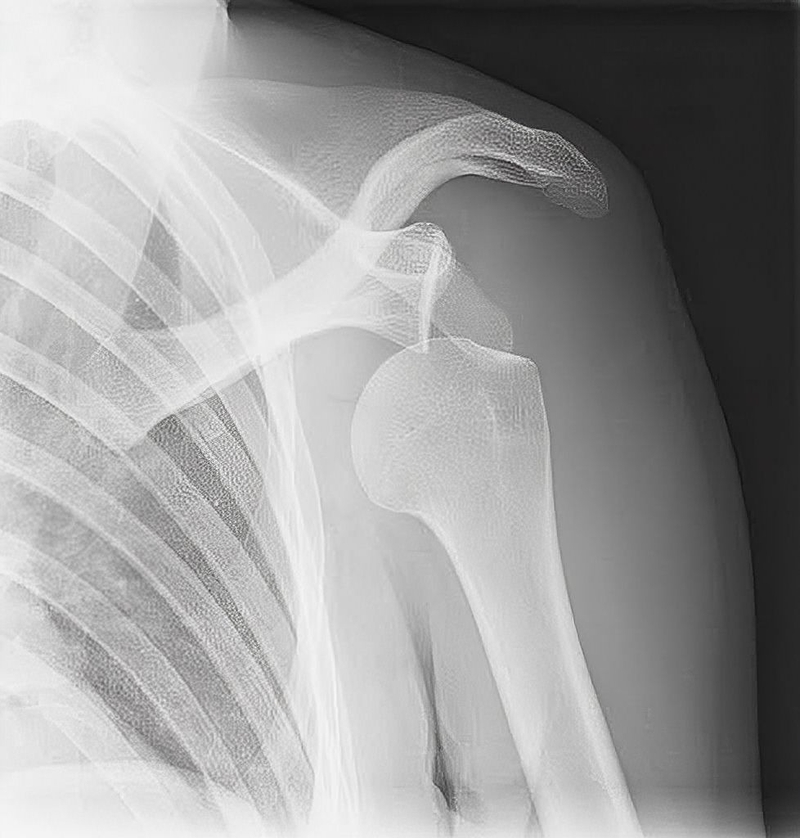

Trật khớp có tự khỏi được không? -1

Trật khớp vai là tình trạng thường xuyên xảy ra

Trật khớp có tự khỏi được không? -2

Trật khớp có tự khỏi được không hay lúc nào cần đi khám

Trật khớp có tự khỏi được không? -3

Một số trường hợp trật khớp cần đến cơ sở y tế để điều trị